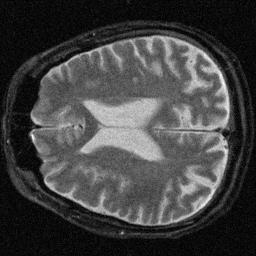

The resolution loss is measured relative to the FWHM of the noisy image, consequently its resolution loss is 0%. Interesting is that the CNR mirrors changes in the SNR, as expected. Also interesting is that the contrast filter reduced the SNR dramatically while actually improving the image resolution. The following images were obtained after filtering:

Correlation Filter